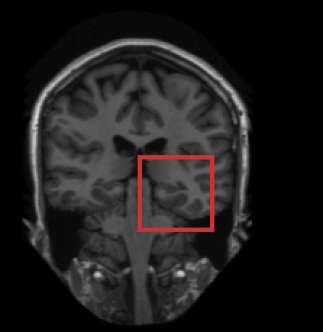

A single CNN is trained to segment six tissues in MR brain images, the pectoral muscle in MR breast images, and the coronary arteries in cardiac CTA. The CNN therefore learns to identify the imaging modality, the visualised anatomical structures, and the tissue classes.

Brain MRI –

34 T1-weighted MR brain images from the OASIS project [9] were acquired on a Siemens Vision 1.5 T scanner, as provided by the MICCAI challenge on multi-atlas labelling [8]222https://masi.vuse.vanderbilt.edu/workshop2012. The images were acquired with voxel sizes of 1.01.01.25 mm3 and resampled to isotropic voxel sizes of 1.01.01.0 mm3. The images were manually segmented, in the coronal plane, into 134 classes that were, for the purpose of this paper, combined into six commonly used tissue classes: white matter, cortical grey matter, basal ganglia and thalami, ventricular cerebrospinal fluid, cerebellum, and brain stem.

Fig. 2 shows the results of the described quantitative analysis, performed at intervals of 1000 mini-batches per task. As the networks learned, the obtained Dice coefficients increased and the stability of the results improved. For each segmentation task, the learning curves were similar for all experiments. Nevertheless, slight differences were visible between the obtained learning curves. To assess whether these differences were systematic or caused by the stochastic nature of CNN training, the training experiment using only brain MR data (Experiment 1) was repeated (dashed line in Fig. 2), showing similar inter-experiment variation. Fig. 3 shows a visual comparison of results obtained for the three different tasks. For all three tasks, all four networks were able to accurately segment the target tissues.